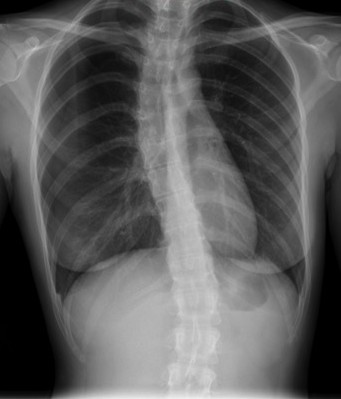

CASO: Febrícula y tos de 4 días de evolución.

Hallazgos:

- En la placa PA se observa una asimetría en los hilios pulmonares, el hilio izquierdo tiene una densidad aumentada.

- Tras examinar la placa lateral se observa un aumento de densidad en la columna que puede ser compatible con una condensación, es el signo de la desnificación vertebral.

SIGNO DE LA DENSIFICACIÓN VERTEBRAL: En la radiografía lateral normal, la densidad de la columna torácica tiende a disminuir desde la parte superior hasta el diafragma; la alteración de ese patrón por la presencia de una densidad superpuesta a la columna, indica la existencia de una consolidación pulmonar. Este signo adquiere especial valor cuando en la proyección posteroanterior la consolidación está oculta en el espacio retrocardíaco o en la base pulmonar.